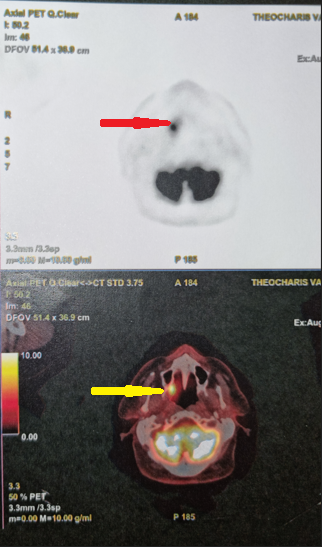

PET scan ολόκληρου σώματος. Παθολογική πρόσληψη στη δεξιά υπερώια αμυγδαλή (Ευγενική παραχώρηση Dr. V. Penopoulos)

PET Scan. Μεταστατικό καρκίνωμα στη δεξιά υπερώια αμυγδαλή (Ευγενική παραχώρηση Dr. V. Penopoulos).